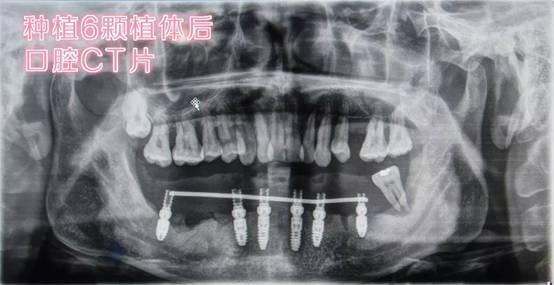

经过病情分析和商讨,曾院长决定为我先治疗牙周病,将下半口已经松动的牙齿进行拔除,然后进行即刻负重种植牙手术。而即刻负重种植牙手术,就是能够实现即拔即种,并即种即食的手术。

听起来就很高科技的感觉是不是,其实这样的手术在贝恩已经有过三百多例了,是因为贝恩拥有独自的牙膜制作间和强大的厂家合作商,运用特有的数字化种植方法,实现数字化种植设计,临床治疗,加工设计一站式完成,为每一位缺牙者提供舒适、安全、高效的来自国际种牙服务,省去长时间等待,也减轻了患者心理负担。